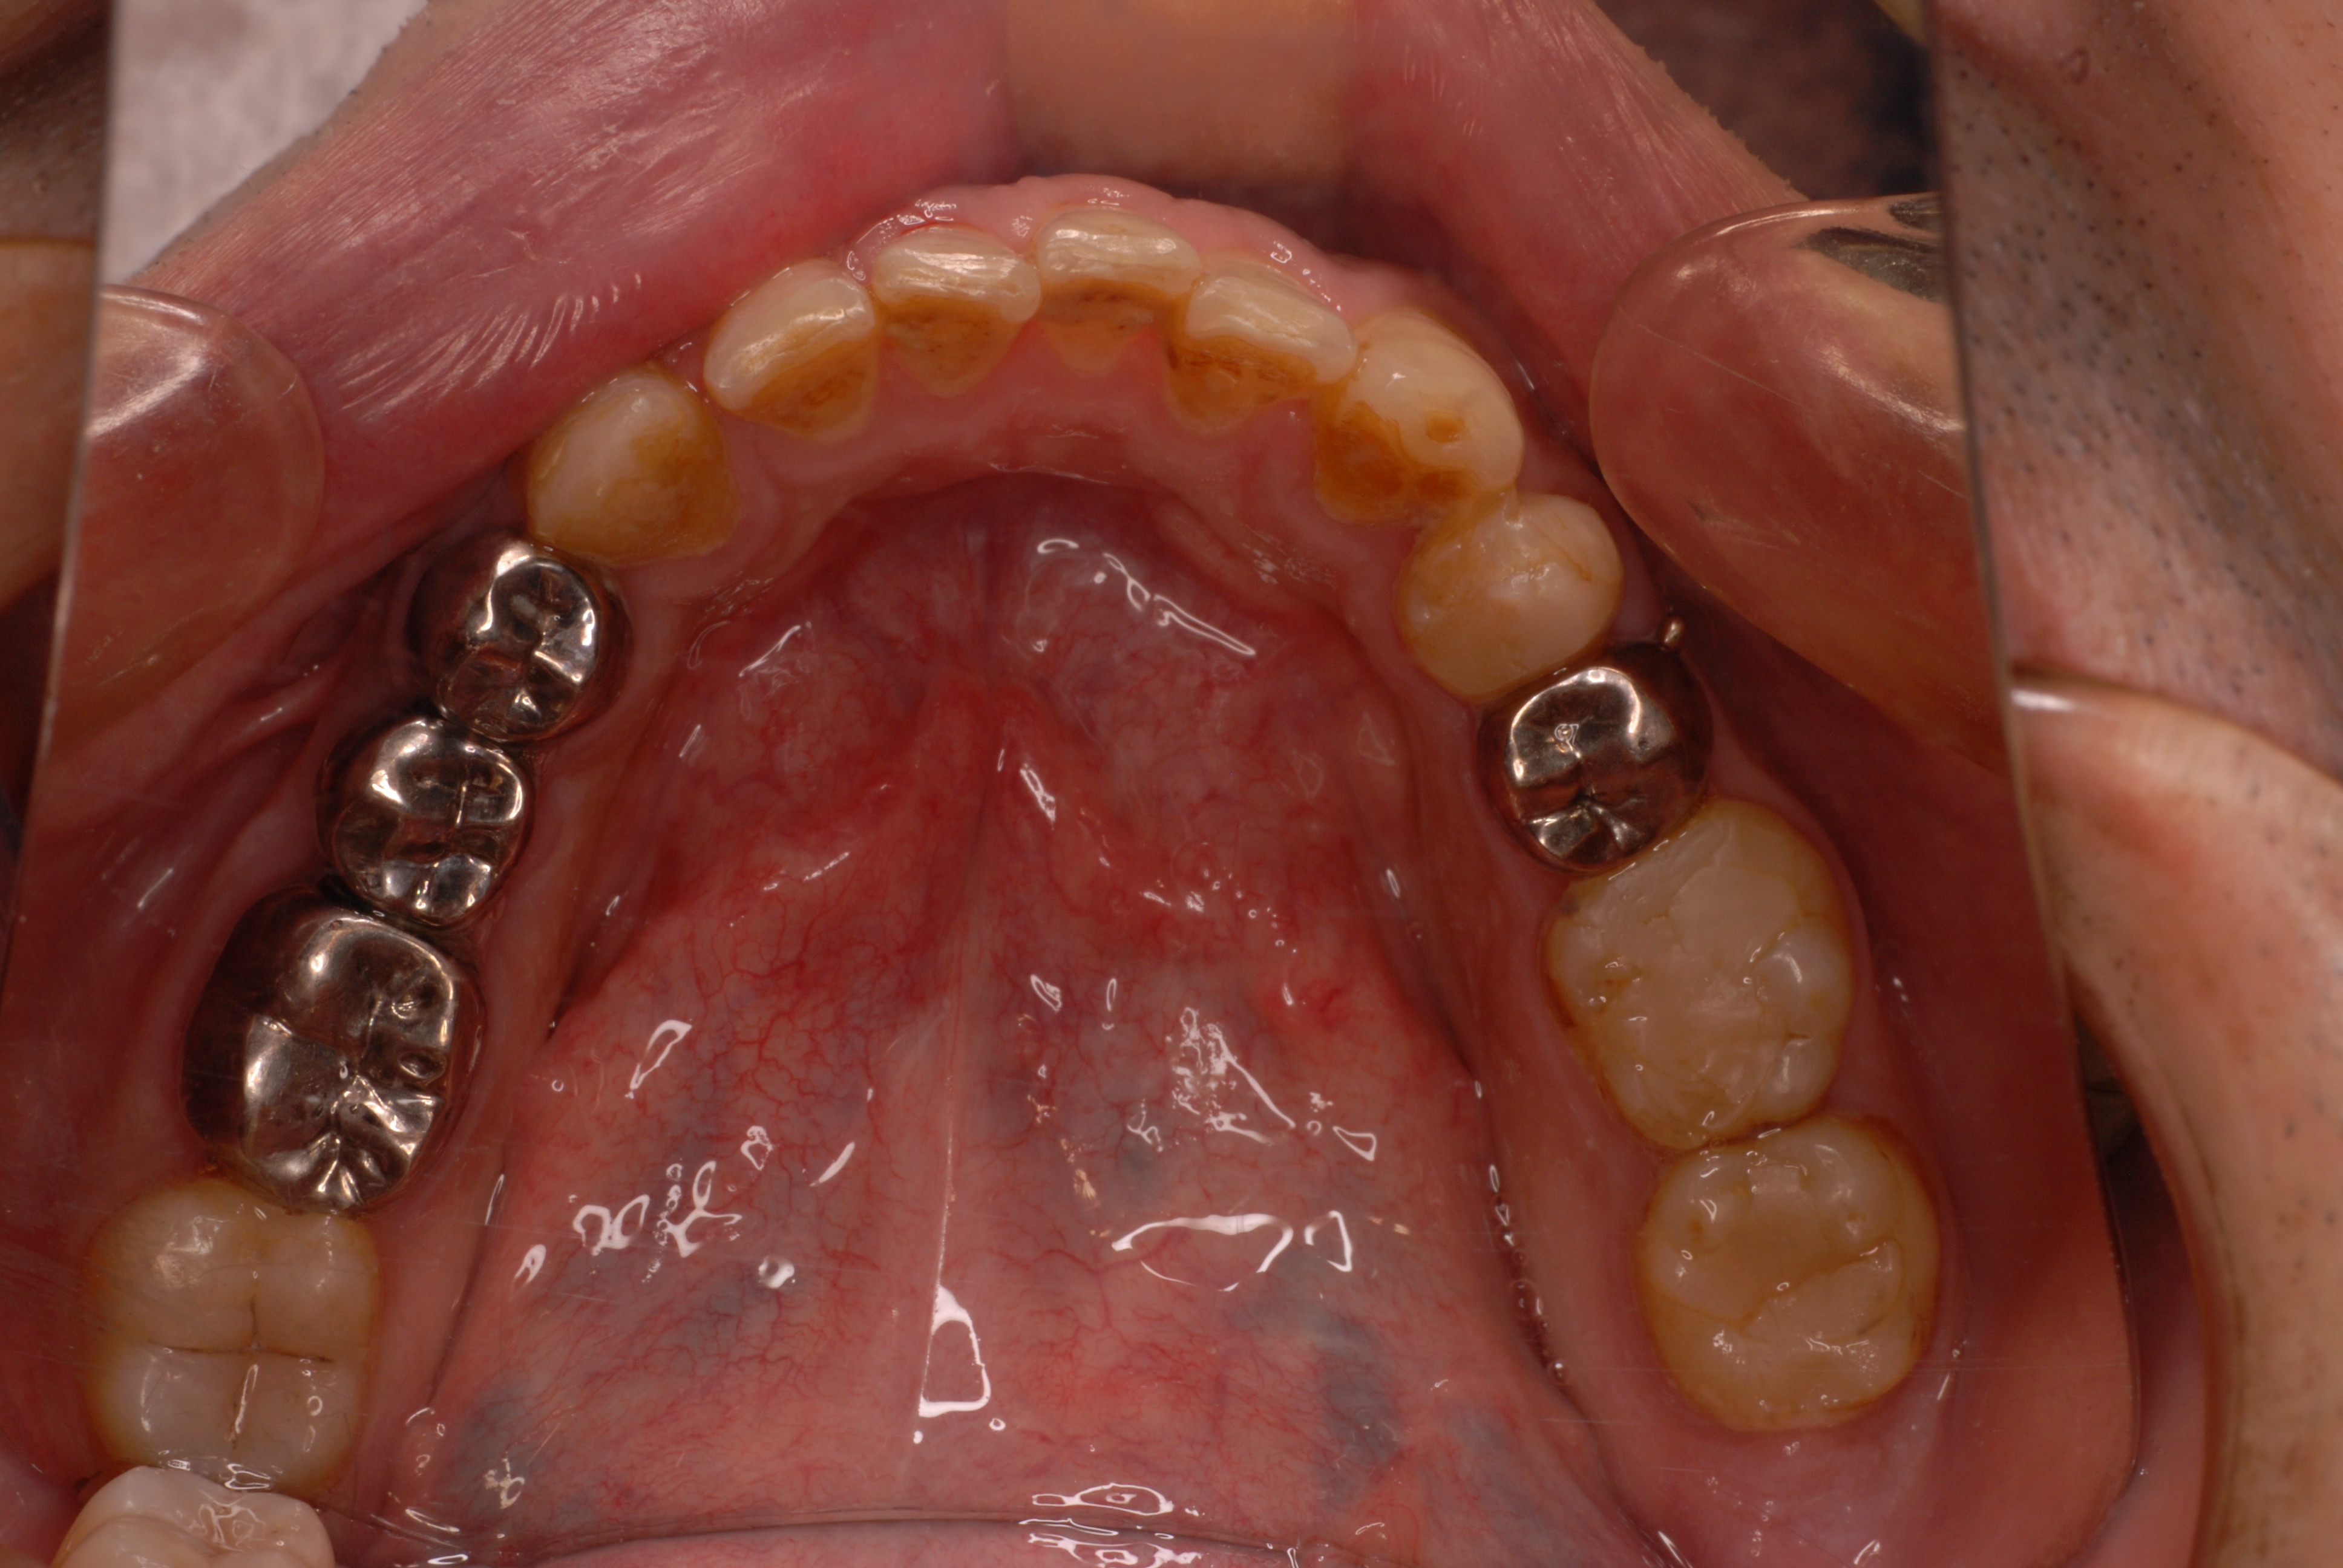

歯無しにならない長い話し

今回約1年近くかかった方のとりあえずの治療が終了しました。

そしてひとまず終了した状態です。

DSC_0018DSC_0023

DSC_0027

このように綺麗になりましたが元の健康な状態になったのではないのです。ばい菌が歯の周りから採れていなければ元の木阿弥。

おそらく差し歯にもできず入れ歯かインプラントという人工歯根になる事でしょう。いやはやいくら費用がかかるのやら患者さんのことながらため息が出ます。

歯医者では病気を治していないことが多いのです。ただ詰めたり被せたりしているのに過ぎません。注意しないともっとひどいことになります。

そして、虫歯や歯周病、そして神経の処置は医療行為ですから誰でも100%うまくいくかというと、うまくいっていないことが多いのです。医療行為は難しいのです。良い歯の医者に当たる事を祈ります。

歯に何かを被せることは医者のやることではなくお口の大工さんがやることなのです。ですから歯医者は、大工と医者を同時にやっていることになりますね。

歯医者から口腔科の医師へ脱皮しなければなりません。日々精進あるのみ!